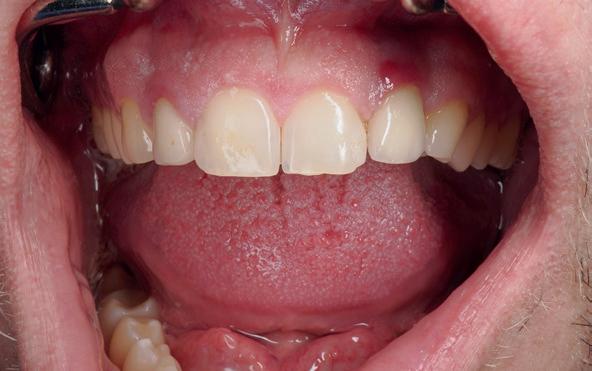

Implantologische behandelingen in het esthetische front vragen meer dan technische vaardigheid alleen. Ze vragen om overzicht, timing, vertrouwen en een team dat als vanzelf samenwerkt onder druk. Juist bij complexe casussen, waarin angst, infectie en hoge esthetische verwachtingen samenkomen, wordt zichtbaar hoe bepalend de rol van de tandartsassistent is.

Deze casus beschrijft een uitgebreide immediate implantaatbehandeling bij een patiënt die door meerdere collega’s werd geweigerd. Niet omdat de mogelijkheden ontbraken, maar omdat de complexiteit vroeg om een perfect afgestemde samenwerking. Het verhaal laat zien hoe de assistent in zo’n traject veel meer is dan een uitvoerende kracht of “mal”, maar een dynamische surgical guide die het proces mede stuurt, bewaakt en mogelijk maakt.De patiënt: wanneer alles samenkomt

Ze kwam binnen op een dinsdagochtend, iets voor achten. Een vrouw van begin zeventig, met een zachte stem en ogen die meer vertelden dan haar woorden. Ze vertelde dat ze een eigen B&B had en dat ze zich nauwelijks kon voorstellen gasten te ontvangen zonder tanden. Op dit moment kon ze echter nauwelijks lachen. “Het doet pijn… en het ruikt soms ook niet goed,” zei ze bijna verontschuldigend. Haar oude bovenbrug, die ze al meer dan twintig jaar droeg, was langzaam maar zeker ingestort. Er was sprake van cariës onder meerdere pijlers, pusafvloed,

chronische ontsteking en een brug die mobiel was en elke beet pijnlijk maakte. Ze had inmiddels meerdere tandartsen bezocht. Drie hadden haar geweigerd. Te complex. Te veel wensen. Te onvoorspelbaar.

De kern van haar vraag was eenvoudig en tegelijkertijd uitdagend: Is het mogelijk om mijn huidige brug te dupliceren en een nieuwe brug te vervaardigen met minder complicaties?

De basis van een complexe beslissing

Mijn behandelplan begint altijd met een uitgebreid klinisch onderzoek. Dat omvat een medische anamnese, intra- en extra-orale camerafoto’s en uitgebreid verwachtingsmanagement. In deze fase is mijn assistent vooral bezig met het zorgvuldig vastleggen van alle gegevens. Juist dat nauwkeurig documenteren zorgt voor rust in de behandelkamer. Minstens zo belangrijk is het luisteren naar de patiënt. Niet alleen naar de klachten, maar naar het

1. Extra-orale foto (lachlijn).

2. Beoordeling van zacht weefsel en botcontour.

3. Reflectiefoto – beoordeling van occlusievlakken en tandboog.

4. Pre-chirurgische OPG.

levensverhaal en de mens achter de brug. Begrijpen wat deze behandeling voor iemand betekent, is cruciaal voor het uiteindelijke succes.

Na het klinische onderzoek volgde het röntgenologisch traject. De CBCT liet precies zien wat we al vreesden: een front waarin het bot onregelmatig was, duidelijke radiolucenties rond de pijlers en een infectiegebied dat zich onder vrijwel de gehele brug had verspreid. Tegelijkertijd was er ook potentie. Net voldoende botstructuur om immediate implantaatplaatsing te overwegen, mits alles perfect gepland zou worden.